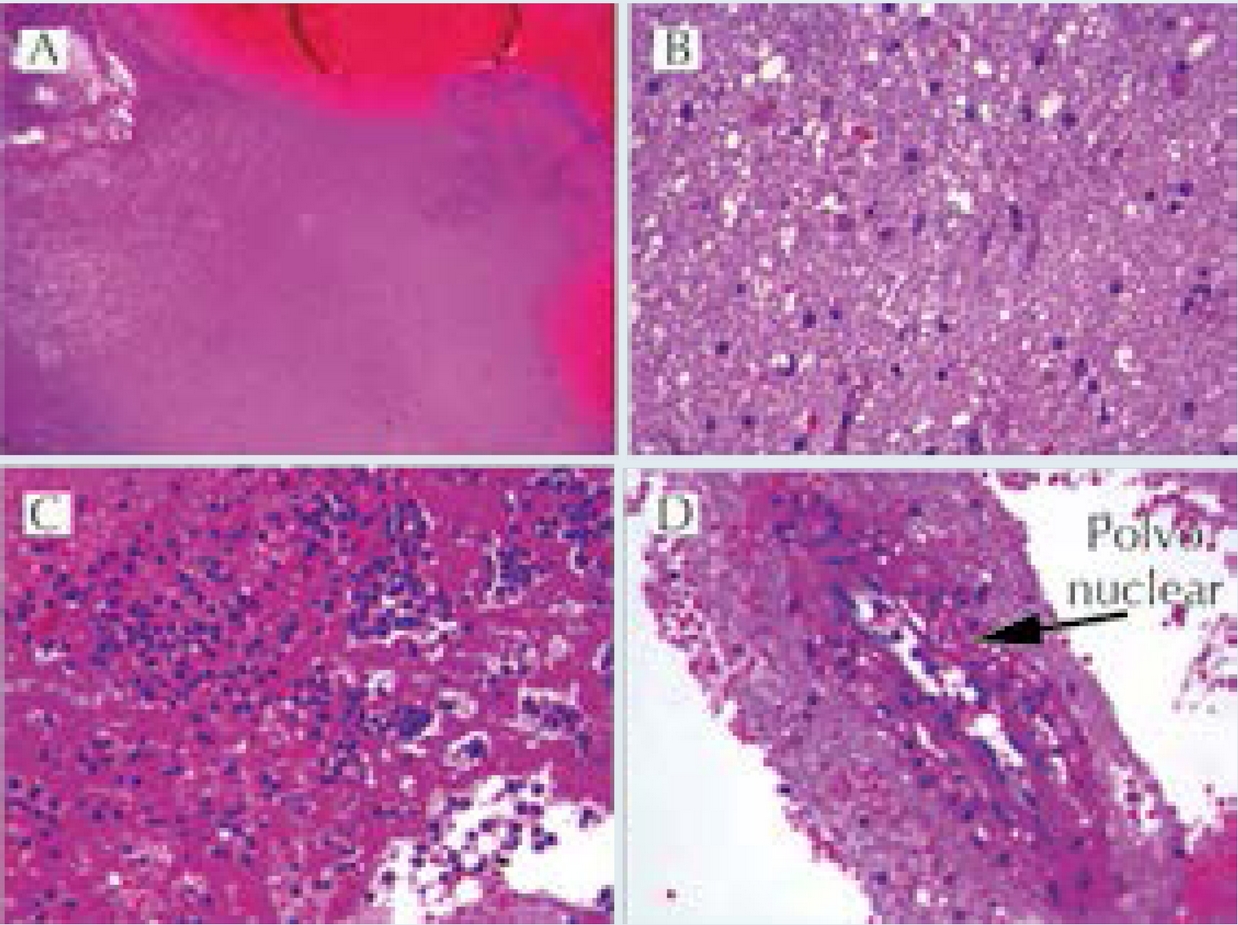

La ultrasonografía ocular reportó una lesión heterogénea que ejercía compresión y desplazamiento en sentido anterior del globo ocular derecho, y datos de inflamación de tejidos blandos (Figura 1). La tomografía computada describió la lesión como heterogénea e identificó datos de sinusitis y proptosis (Figura 2). Por resonancia magnética se reportó la misma lesión con aspecto heterogéneo de 5.5 ' 2.5 cm en sus diámetros mayores, que involucró tejidos musculares y con efecto de masa sobre estructuras orbitarias. No se observó extensión intracraneal, a cavidades paranasales ni al seno cavernoso (Figura 3). Ante una proptosis de rápida evolución y sospecha de probable rabdomiosarcoma se realizó biopsia transconjuntival de lesión intraconal y tejido peri-orbitario. Las preparaciones histológicas de la lesión intraconal y de la grasa orbitaria mostraron tejidos blandos con un proceso inflamatorio, necrótico con vasculitis de vasos de pequeño calibre con afección ocasional a vasos arteriales y venosos de mayor calibre. La vasculitis fue a expensas de linfocitos e histiocitos con trombosis aislada y algunos granulomas mal constituidos. El proceso inflamatorio estaba constituido por linfocitos, histiocitos, células plasmáticas y en una zona se mezclan con numerosos neutrófilos con cariorexis; la necrosis fue isquémica. Se realizaron diversas tinciones de histoquímica convencional e inmunohistoquímica para descartar neoplasia linfoide maligna o proceso infeccioso granulomatoso como micobacterias u hongos. La glándula lagrimal mostró afección por el proceso inflamatorio, la necrosis isquémica y la propia vasculitis. El diagnóstico fue de: granulomatosis de Wegener (Figura 4).

Figura 4 Biopsia de tejido periorbitario. A) Vasculitis: tinción de fibras elásticas en vaso venoso con infiltrado linfocitario en su pared. B) CD3 marcador de linfocitos T en la pared de la vena. C) Granuloma constituido por histiocitos epitelioides y una célula gigante multinucleada. D) CD68 marcador de histiocitos positivo en granuloma. A-C) Tinción de hematoxilina & eosina a 40X. D) Tinción para inmunoperoxidasa a 40X.

Cinco días después, persistía con fiebre y presentó deterioro neurológico súbito que requirió apoyo mecánico a la ventilación y cuidados intensivos. En el estudio tomográfico se documentó hemorragia aguda intraventricular e intraparenquimatosa (Figura 7). Ingresó a craniectomía descompresiva, drenaje de hematoma (100 mL) y toma de biopsia (Figuras 8 y 9). En las siguientes 2 semanas su evolución no mejoró persistiendo con deterioro neurológico, múltiples sangrados a nivel de sistema nervioso central (Figura 10) y gastrointestinal, así como hemorragia pulmonar masiva con nula respuesta a múltiples intervenciones (i.e.: pulsos de metilprednisolona, inmunoglobulina humana intravenosa, ciclosporina, rituximab, anfotericina B, múltiples transfusiones de hemoderivados, y plasmaféresis). Finalmente presentando falla orgánica múltiple, muerte cerebral y paro cardiorrespiratorio refractario a reanimación cardiopulmonar.

Figura 8 Biopsia de sistema nervioso central mostrando parénquima cerebral. A) Necrosis coagulativa cerebral y hemorragia. B) Gliosis reactiva con cambio microvacuolar en neurópilo. C) Exudado PMN con fibrina. D) Vasculitis focal con leucocitoclasia. Hematoxilina y eosina a 10X y 40X.

Los hallazgos histopatológicos característicos del involucro a nivel de órbita incluyen granulomas focales, depósito de colágeno, necrosis, polvo nuclear, infiltrado de células plasmáticas. La infiltración de eosinófilos se ha propuesto como un factor predictor de progresión de la enfermedad.8